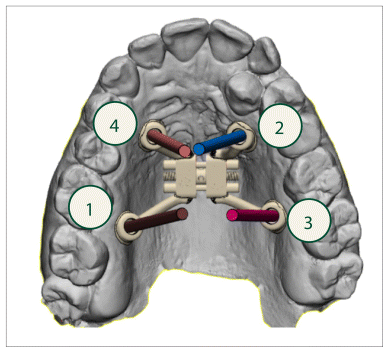

The surgical planning was predicated on high-resolution three-dimensional DICOM imaging, facilitating a comprehensive assessment of the maxillary bone structures and their spatial relationship with the dental roots. The STL file of the patient’s upper arch was acquired and digitally aligned with the CBCT scan, thus enabling accurate anatomical reconstruction and enhancing the virtual planning of screw placement (Figures 1 and 2).

As delineated by Haas Junior et al. (13), the STL file of the expander screw was incorporated and precisely positioned in the desired location. The placement of miniscrews was meticulously planned, maintaining an approximate distance of 1.0 mm from the contour of the palatal mucosa, utilizing the file addition and positioning tool (Figure 1). Particular attention was given to the correct orientation of the screws (Figure 2), ensuring respect for anatomical structures, thereby avoiding injury to the dental roots or periodontal tissue, and guaranteeing an appropriate insertion depth into the bone.

Subsequently, a three-dimensional reconstruction of the processed data was carried out to acquire a spatial overview of the relationships between the planned anchorage screws and the roots of the dental elements in the upper arch (Figure 3). The positioning methodology guaranteed the optimal allocation of expansion forces while minimizing potential risks to neighboring dental roots.

A customized palatal expander has been manufactured utilizing additive manufacturing techniques. It comprises a region containing an expansion screw and fixation arms anchored to the palatal bone, as well as a dental guide that was removed following stabilization to ensure the accurate positioning of the device.